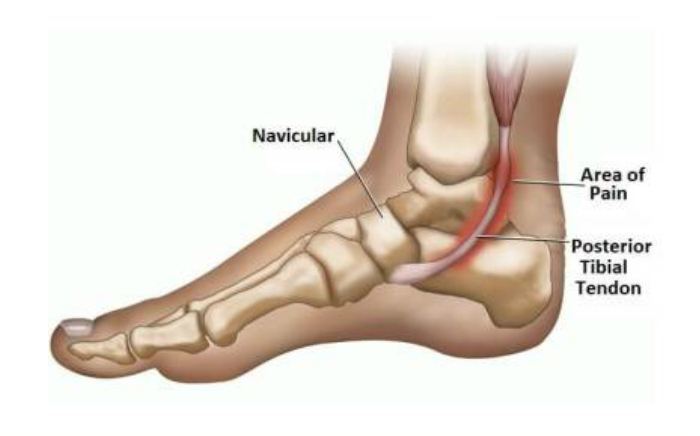

Common Foot & Ankle Disorders

Did you know the foot has 26 bones, 33 joints, 107 ligaments, 19 muscles, and numerous tendons? These parts all work together to allow the foot to move in a variety of ways while balancing your weight and propelling you forward or backward on even or uneven surfaces. It is no wonder that 75 percent of all Americans will experience foot problems at one point or another in their lifetimes.